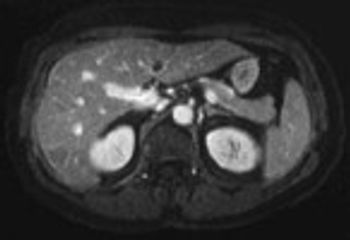

University of Pennsylvania researchers have developed an experimental MRI contrast agent capable of targeting tumors, according to a report in the journal ACS Nano. Its coating, instead of targeting particular cancer receptors - which can be hit-or-miss and depend on the cancer - is attracted to the acidic environments in which tumors generally thrive.